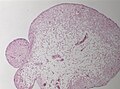

Histology

Surgery depends on clinical symptoms due to CSF obstructions. Specimens may include: [5]

• Vertebral bone (decompression)

• Hermiated cerebellar tonsils.

• Reactive / dysplastic choroid plexus.

• Glial nodules.

• Arachnoidal cysts.

• Subependymomas.

In cases with myelomeningocele at autopsy, the posterior fossa should be examined.

Images